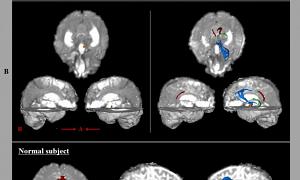

למרות זאת, להפתעתם, זה לא קרה. למעשה, אחד ההיבטים הבולטים ביותר היה שאזורי המוח של אותה המיספרה היו יותר ויותר מחוברים זה לזה בששת האנשים האלה עם חצי מוח בלבד מאשר אצל האנשים עם המוח שלהם שלם.

זה הצביע על כך שיש להם גם יכולת קוגניטיבית גדולה יותר, יותר כישורים חברתיים, והפגינו ביצועים טובים יותר באופן כללי. עם זאת, מכיוון שרק שישה אנשים נחקרו, לא ניתן להכליל את התוצאות.